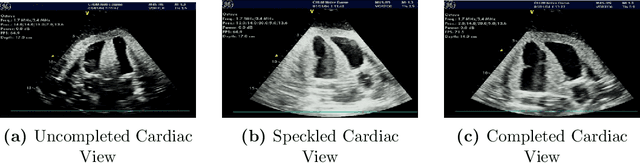

Abstract:Cardiac ultrasound (US) scanning is a commonly used techniques in cardiology to diagnose the health of the heart and its proper functioning. Therefore, it is necessary to consider ways to automate these tasks and assist medical professionals in classifying and assessing cardiac US images. Machine learning (ML) techniques are regarded as a prominent solution due to their success in numerous applications aimed at enhancing the medical field, including addressing the shortage of echography technicians. However, the limited availability of medical data presents a significant barrier to applying ML in cardiology, particularly regarding US images of the heart. This paper addresses this challenge by introducing the first open graded dataset for Cardiac Assessment and ClassificaTion of UltraSound (CACTUS), which is available online. This dataset contains images obtained from scanning a CAE Blue Phantom and representing various heart views and different quality levels, exceeding the conventional cardiac views typically found in the literature. Additionally, the paper introduces a Deep Learning (DL) framework consisting of two main components. The first component classifies cardiac US images based on the heart view using a Convolutional Neural Network (CNN). The second component uses Transfer Learning (TL) to fine-tune the knowledge from the first component and create a model for grading and assessing cardiac images. The framework demonstrates high performance in both classification and grading, achieving up to 99.43% accuracy and as low as 0.3067 error, respectively. To showcase its robustness, the framework is further fine-tuned using new images representing additional cardiac views and compared to several other state-of-the-art architectures. The framework's outcomes and performance in handling real-time scans were also assessed using a questionnaire answered by cardiac experts.